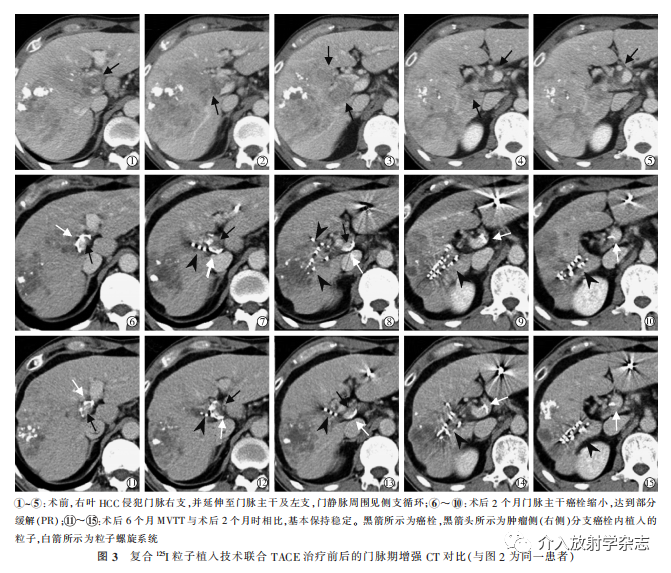

每例患者门静脉主干内各植入1枚粒子螺旋系统,24例患者共植入24枚粒子螺旋系统;粒子螺旋系统植入门静脉后呈螺旋状自行固定于主干癌栓旁,其长度覆盖主干癌栓近远端(图2);主干癌栓接受的平均D90为(40.2±3.6) Gy。肿瘤侧分支癌栓内粒子植入后,125I粒子位于分支癌栓内,并沿着分支癌栓的纵轴方向排列(图2⑤⑥,图3);分支癌栓接受的平均D90为(84.5±7.1) Gy。

本研究随访时间为1.4~34.2个月。MPVTT的 ORR和DCR分别为54.2%(13例部分缓解)和87.5%(13例部分缓解,8例稳定);肝内病变ORR和DCR分别为29.2%(7例部分缓解)和37.5%(7例部分缓解、2例稳定)(图3)。中位生存期为(9.5±1.4)个月(95%CI,6.7~12.3个月)。